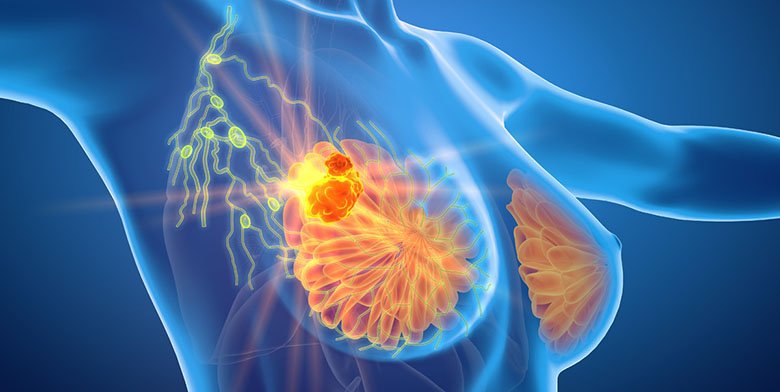

The statistics on breast cancer recurrence is not calming. More than 30% of women who have lived through this disease have to fight with it for the second time. Half of the cases happen in more than 5 years after the tumor removal surgery. Such figures make the scientists all over the world look for an effective and financially available treatment to help women escape the sad statistic.

The main aim of the trial was to reach the lowering of the number of the stem cells, which are actually responsible for the problem. The patients were taking the drug for two weeks prior to the surgery. Based on the results of tests that were received, the number of aggressive cells has significantly dropped by 17% – 66% in 90 percent of the patients.

Doxycycline affects the main power generator of the cell – mitochondria. By inhibiting its function, the drug prevents the stem cell division. Such a mechanism of action prevents the recidivism of breast cancer and the growth of the metastases in the post-surgery period.